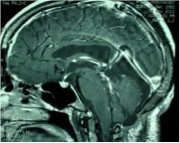

Pre

Post